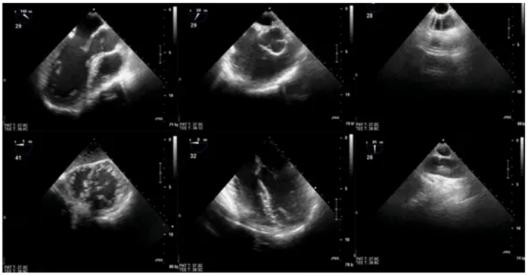

TEE监测可从形态和功能两个方面评估循环系统,具有定时、定位、定性、定量的基本功能,适用于血容量监测,整体和局部左心功能、右心功能评价,监测基本的瓣膜形态及功能变化,成人常见的先心病的形态和功能监测等。

TEE监测的应用要求实现TEE图像的3个标准化,即切面标准化、评估标准化和决策标准化,其局限性主要体现在以下几方面。

注:1.左心室长轴切面;2.右心室流入流出道切面;3.降主动脉短轴切面;4.经胃底心室短轴切面;5.食管中段四腔心切面;6.升主动脉长轴切面(中华医学会麻醉学分会超声学组2014年推荐)

图4 目标导向TEE监测的6个基本切面(Focused-TEE)